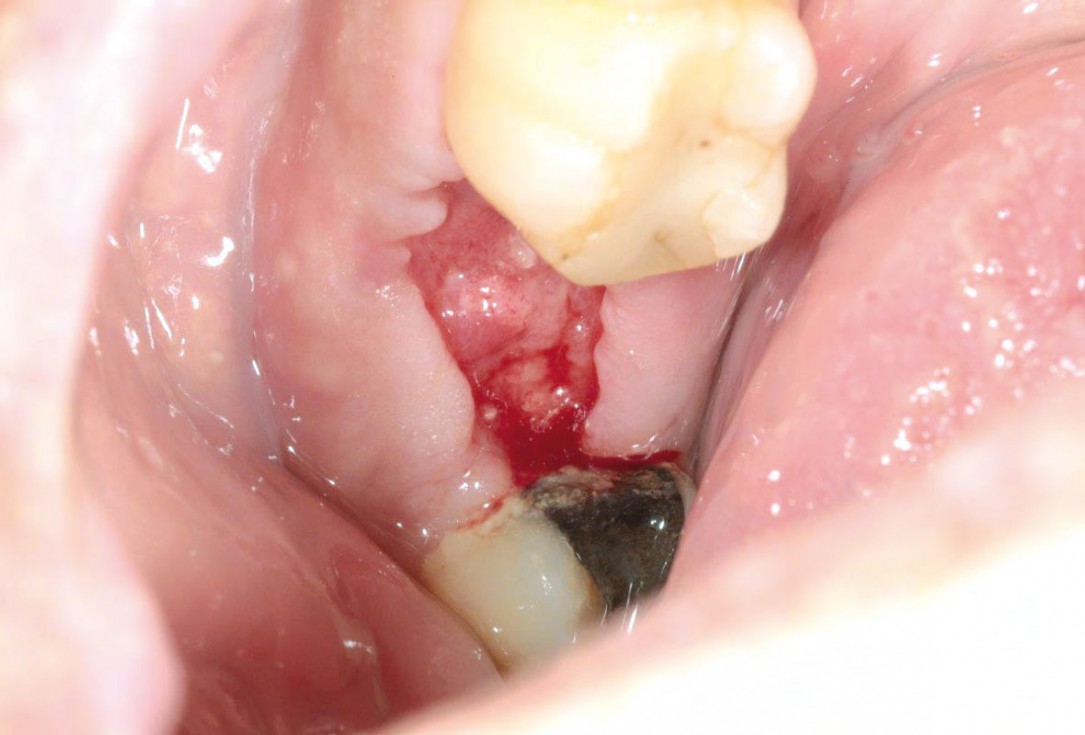

Initial situation: missing teeth #11 & 12 and badly broken #21 root